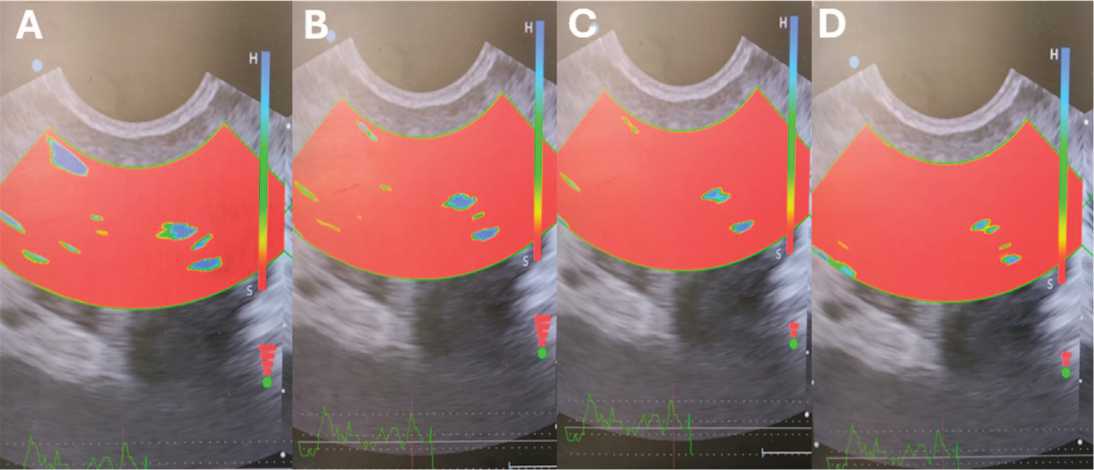

В динамике (18–54-я недели) во всех группах зафиксировано уменьшение числа кальцинатов и зон фиброза,рост областей нормальной эластичности и увеличение скоростных показателей артериального кровотока. Наиболее выраженные положительные изменения регистрировались в третьей группе (рис. 2).

Рис. 2. Динамика картины соноэластографии предстательной железы в группе 3 до и после лечения: А – 0 неделя; В – 18 неделя; С – 30 неделя; D – 54 неделя

Fig. 2. Dynamics of the sonoelastography pictures of the рrostate in group 3 before and after treatment: A – 0 week; B – 18th week; C – 30th week; D – 54th week